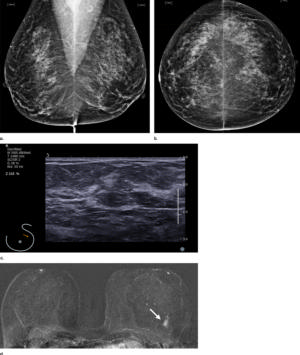

Figure 1. Images in a 55-year-old screening participant. (a, b) Normal digital full-field mediolateral oblique (a) and craniocaudal (b) mammograms (BI-RADS category 1) show a heterogeneously dense breast (ACR category C). (c) Screening ultrasound image shows normal findings (BI-RADS category 1). (d) MR-guided biopsy enabled us to confirm the presence of an invasive high-grade triple-negative cancer (no special type [NST], pT1b, N0, M0). (d) Breast MR image shows a suspicious enhancing mass (arrow) in the left breast (BI-RADS category 5).E

Figure 3. Normal digital full-field mediolateral oblique mammogram (BI-RADS category 1) show a heterogeneously dense breast (ACR category C).

High-res (TIF) version

Figure 4. Normal digital full-field craniocaudal mammogram (BI-RADS category 1) show a heterogeneously dense breast (ACR category C).

Figure 5. Screening ultrasound image shows normal findings (BI-RADS category 1).

Figure 6. MR-guided biopsy enabled us to confirm the presence of an invasive high-grade triple-negative cancer. Breast MR image shows a suspicious enhancing mass (arrow) in the left breast (BI-RADS category 5).